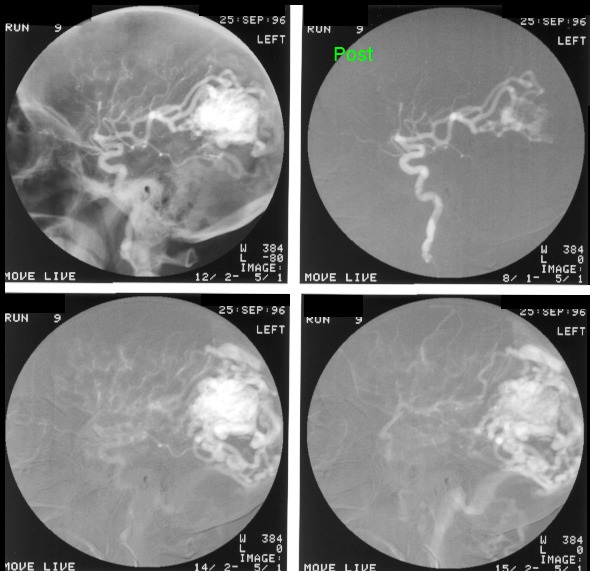

This patient was known to have a vascular cerebral lesion. The patient saw a neurosurgeon operating on a similar patient on TV. She then decided to consult the same surgeon who successfully removed the arteriovenous malformation. Pre-operative embolisation of the arteriovenous malformation made the operation easier and the lesion was excised in 4 hours . Post embolisation images are seen in the top right image.

Embolisation of the branches of the posterior cerebral artery. Note the reduced circulation of the left cerebral hemisphere.

Images showing the location of multiple coils and marked reduction in the blood supply from the internal carotid artery. This procedure allowed the surgical removal of the AVM to be safer and much quicker, the lesion was removed in 4 hours.